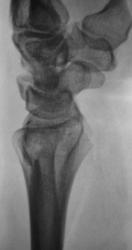

Пациент направлен врачом общей практики (ВОП) на рентгенографию лучезапястного сустава с диагнозом "Перелом?". Произведено стандартное исследование лучезапястного сустава. Выявлен перелом лучевой кости в типичном месте почти без смещения отломков, перелом локтевой кости в области основания шиловидного отростка с незначительным смещением отломков по ширине. Возникает подозрение на разрыв дистального луче-локтевого сочленения. Ваше мнение коллеги?